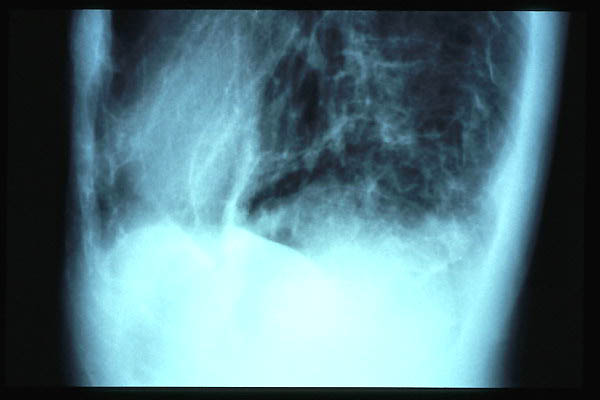

Osteoporosis circunscrita en Enfermedad de Paget.